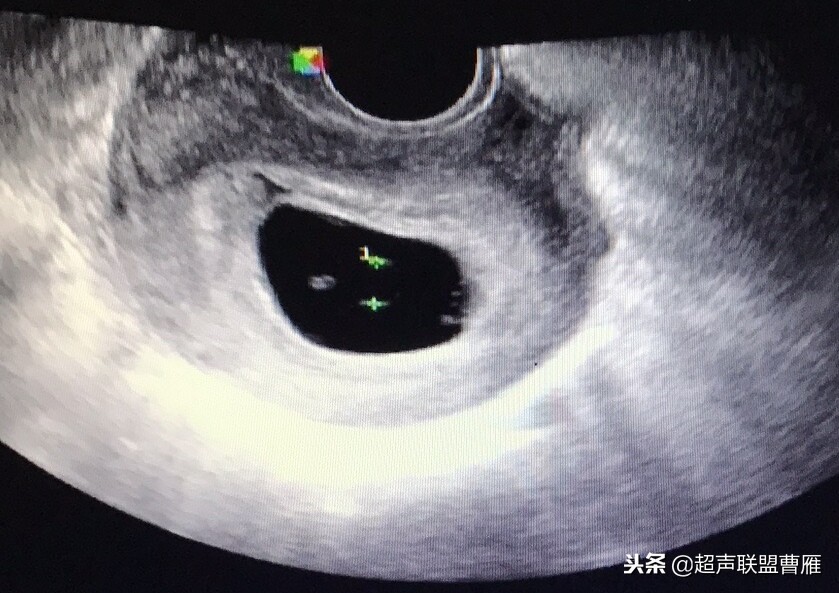

妊娠37天超声检查卵黄囊可以显示,羊膜腔及胚胎不能显示

真实的卵黄囊、胚体及羊膜腔形象

妊娠37天出现卵黄囊

在妊娠妊娠38天前后(36-40)天可以见到卵黄囊。 孕囊在6-9mm的可以见到其中有卵黄囊。

有的图像卵黄囊YS只是两条平行的细短线

卵黄囊高分辨超声图像,妊娠40天